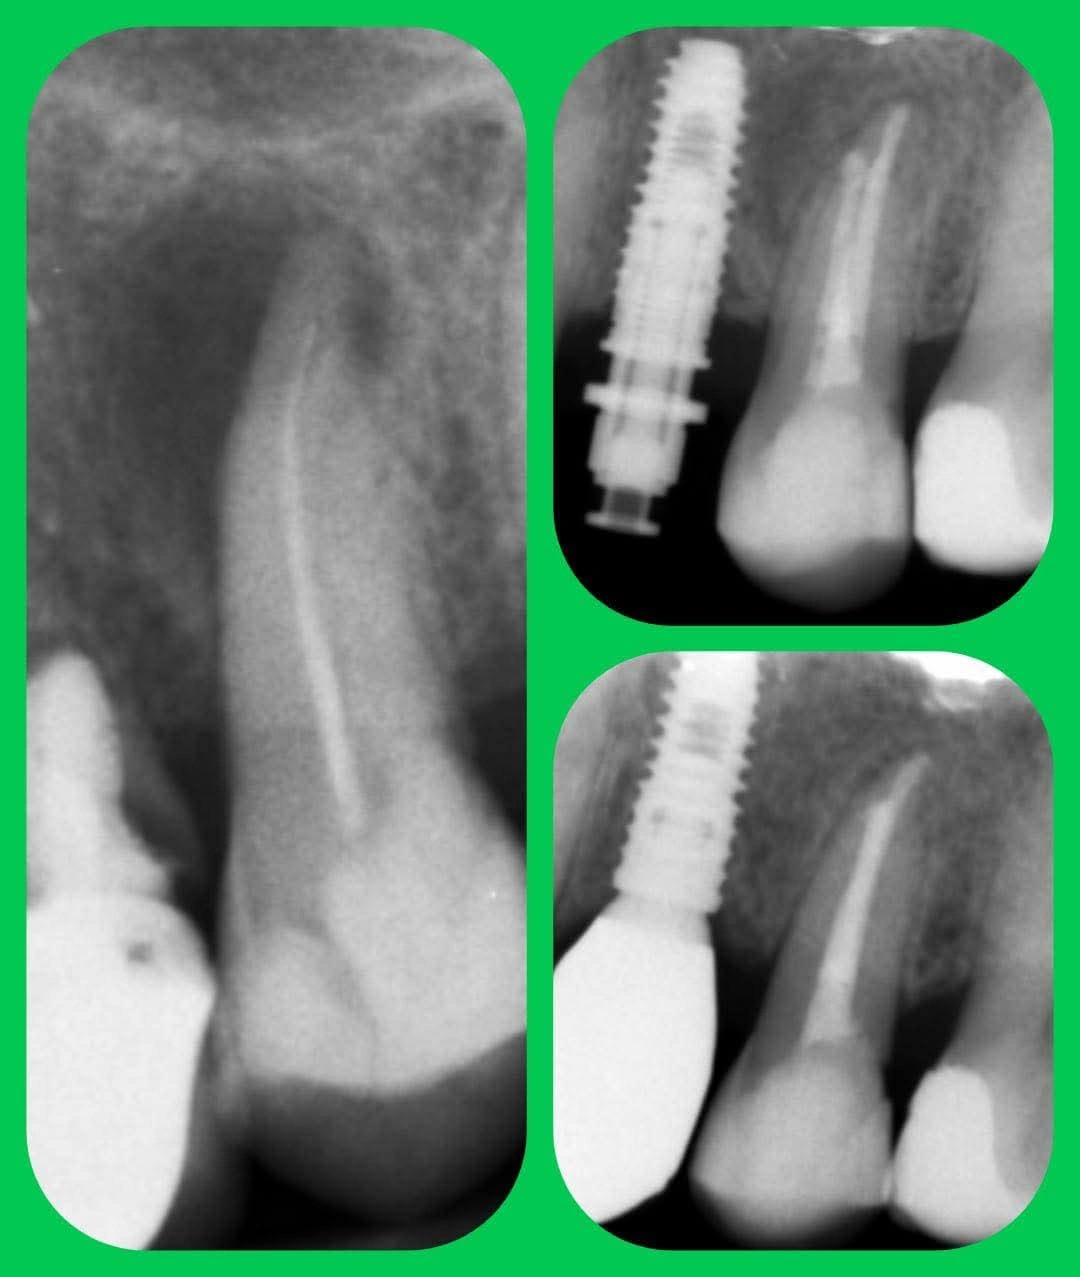

Przykłady wykorzystania mikroskopu w endodoncji:

- odnajdywanie ujść kanałów korzeniowych,

- obecność i lokalizacja kanałów dodatkowych,

- opracowanie cieśni kanałów korzeniowych,

- udrażnianie częściowo zobliterowanych kanałów,

- wypełnianie kanałów korzeniowych,

- ponowne leczenie kanałów ze zmianami zapalnymi wokół wierzchołków korzeni,

- usuwanie złamanych narzędzi kanałowych,

- zaopatrzenie perforacji dna komory lub korzenia.

- diagnostykę i ocenę stanu zęba – przeprowadzamy dokładne badania stomatologiczne, w tym badania RTG, aby zidentyfikować wszelkie problemy wewnątrz zęba i ustalić odpowiedni plan leczenia;

- leczenie kanałowe pod mikroskopem – korzystając z zaawansowanych technik i sprzętu, przeprowadzamy precyzyjne i skuteczne leczenie kanałowe, usuwając zainfekowane tkanki i bakterie oraz zabezpieczając ząb przed dalszym uszkodzeniem;